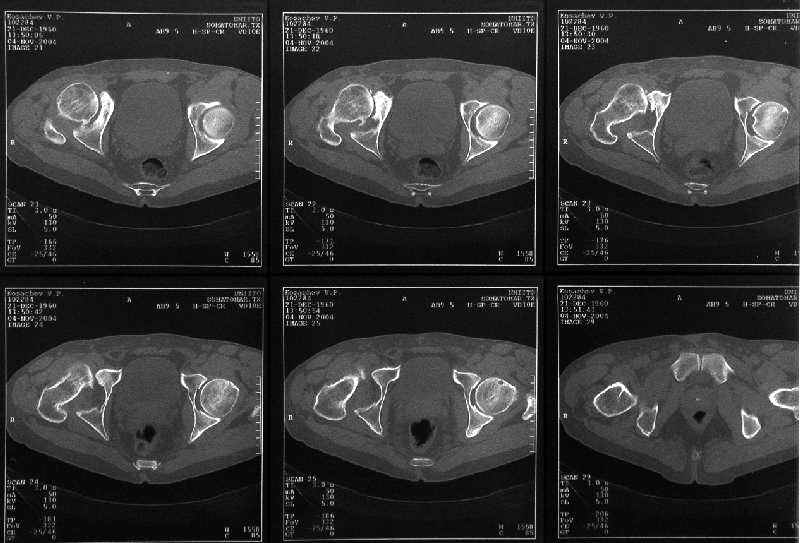

мужчина, 43 лет, получил травму в январе 2001 года. Лечился консервативно, в соседней области: скелетное вытяжение 6 недель, далее в кокситной гипсовой повязке 2 месяца. С декабря 2001 года ходит без дополнительной опоры, с компенсацией имеющегося укорочения - 4 сантиметра. С марта этого года беспокоят боли, усиливающиеся после умеренной физической нагрузки, возникающие в задних отделах таза и переходящие в область тазобедренного сустава. По данным ретгенографии и компьютерной томографии у больного имеется несросшийся высокий двухколонный перелом вертлужной впадины. Заранее спасибо.